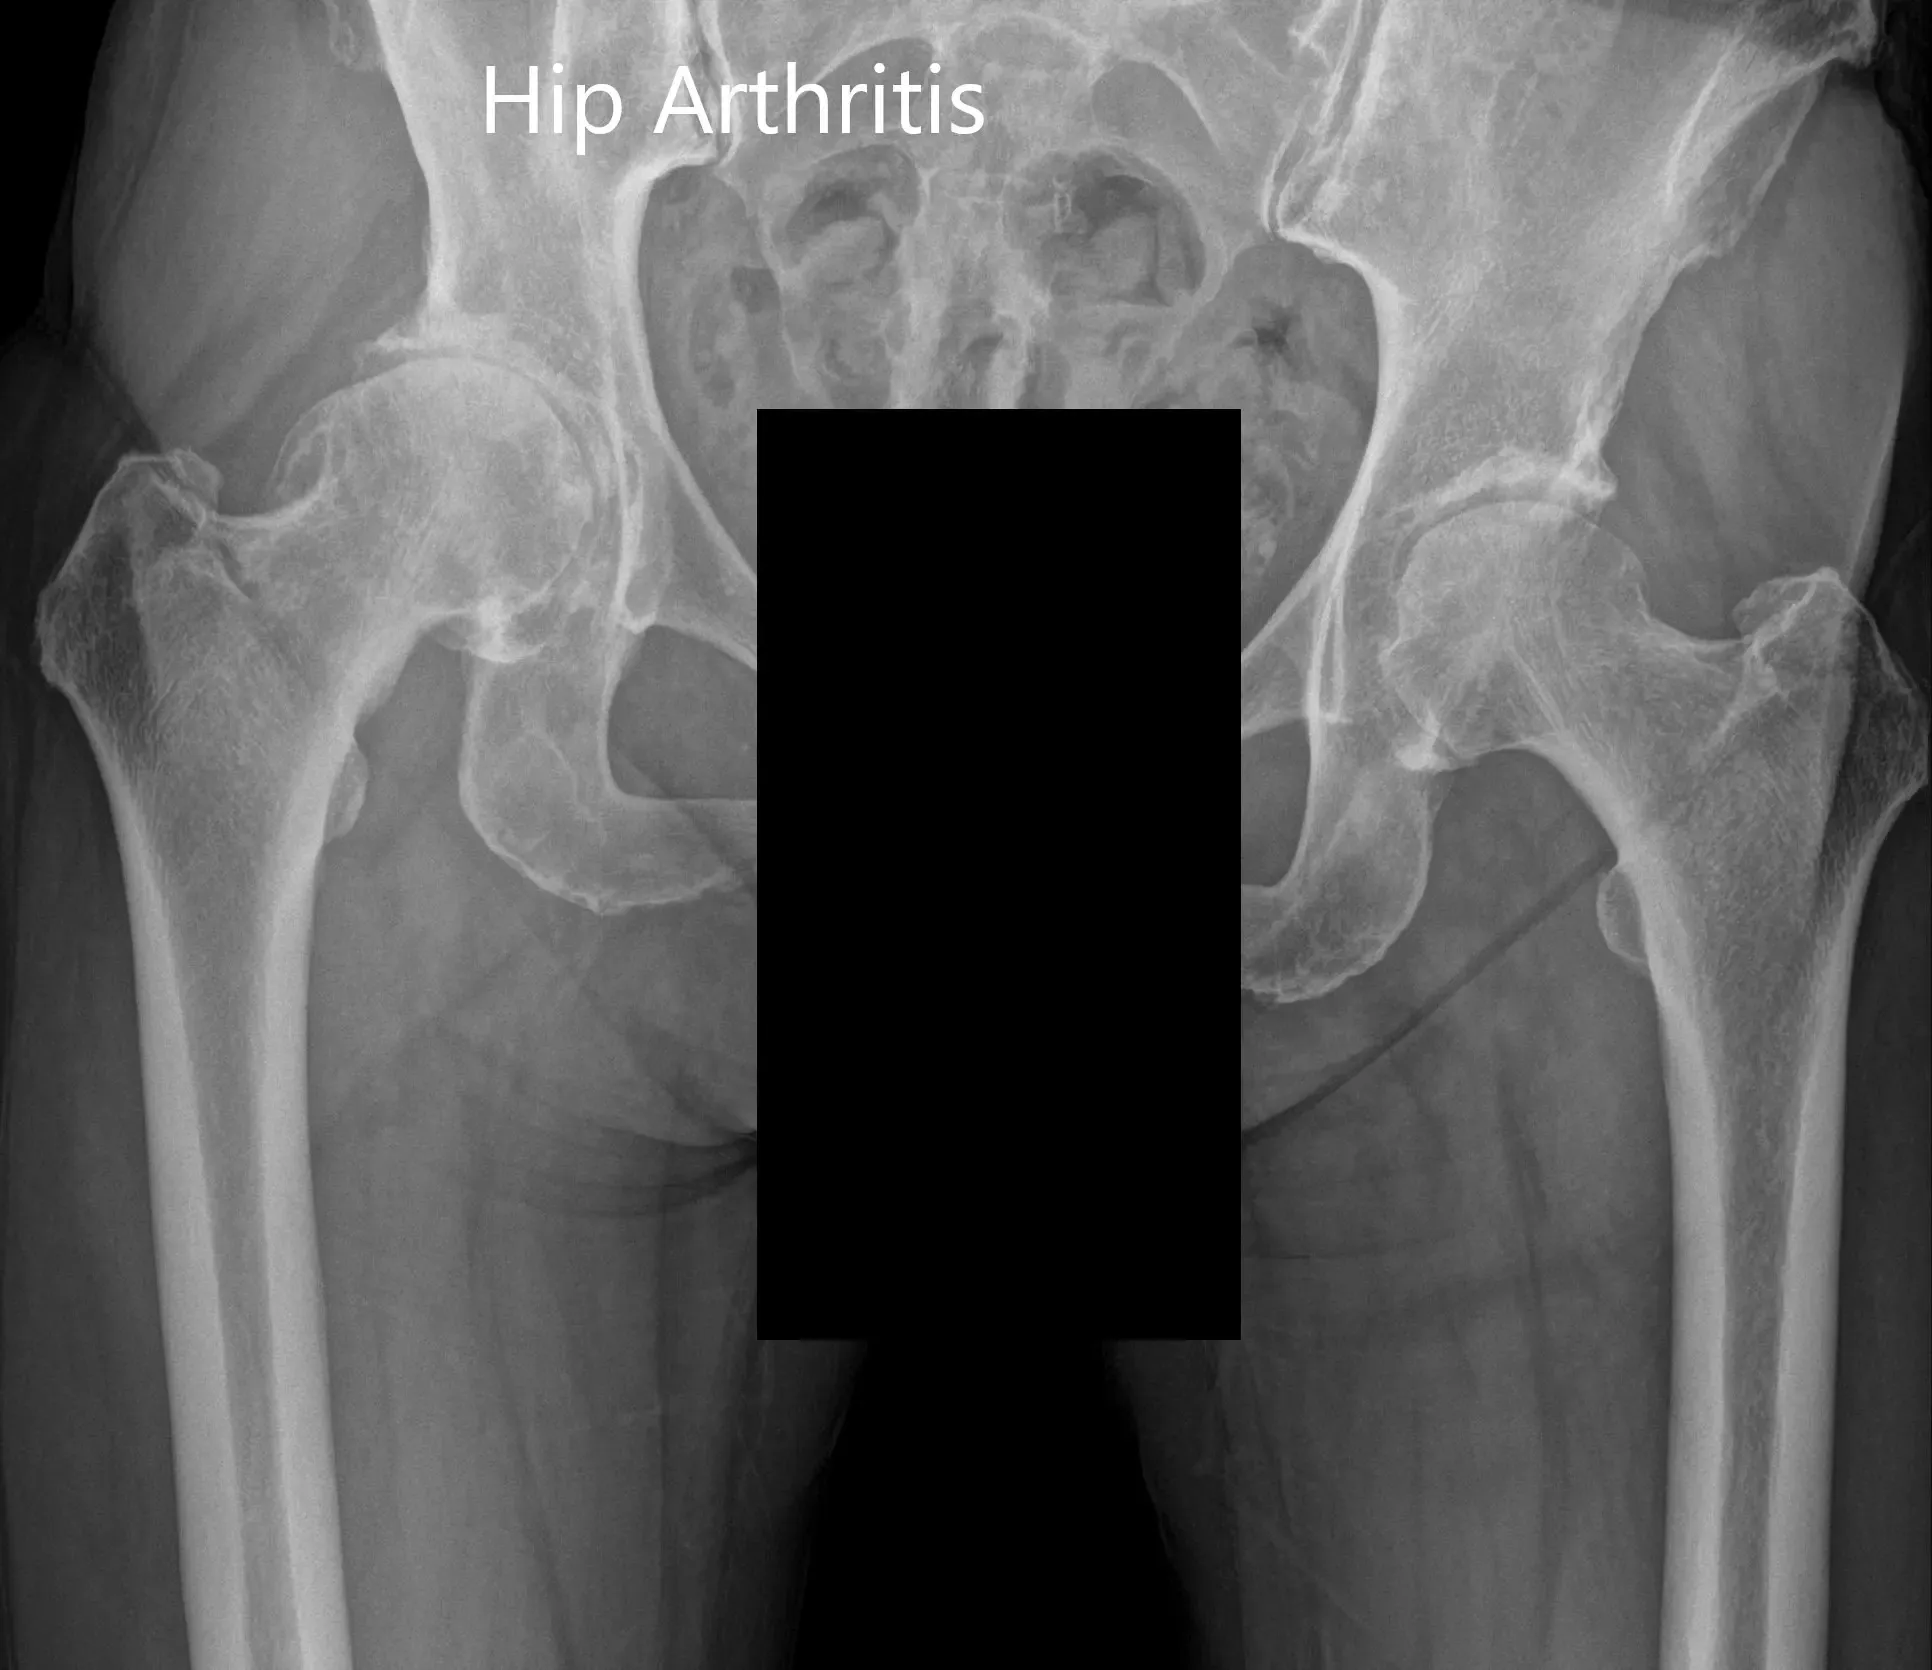

Imaging revealed osteoarthritis of the right hip with joint space reduction and osteophytes. The patient was advised right total hip robotic replacement. The risks, benefits, and alternatives were discussed with the patient at length and she agreed with the plan.

Preoperative X-ray showing the AP view of the pelvis with both hips.